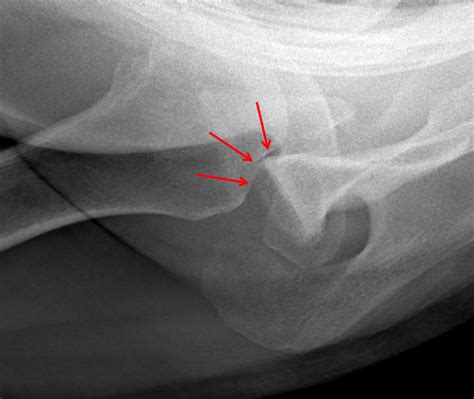

A Hill Sachs Fracture is a specific type of injury that occurs in the shoulder joint. It involves a compression fracture of the humeral head, which is the upper part of the arm bone that fits into the shoulder socket. This fracture typically results from a dislocation of the shoulder, where the humeral head is forced out of its socket and then impacts the glenoid rim, causing a depression or fracture on the humeral head.

• X-rays: These can help identify fractures and dislocations but may not always show the Hill Sachs lesion clearly.

• MRI (Magnetic Resonance Imaging): This provides detailed images of the soft tissues and can help confirm the presence of a Hill Sachs lesion.

• CT Scan (Computed Tomography): This can offer a more detailed view of the bone structure and is often used to assess the extent of the fracture.